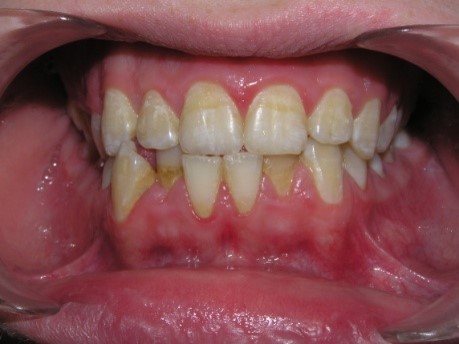

Pic.10. Lingual position of teeth 32 and 42.

The crowding of the lower frontal

teeth reduces the resistance of the teeth to the carious process, creates

conditions for the development of periodontal diseases, and the formation of

periodontal pockets.